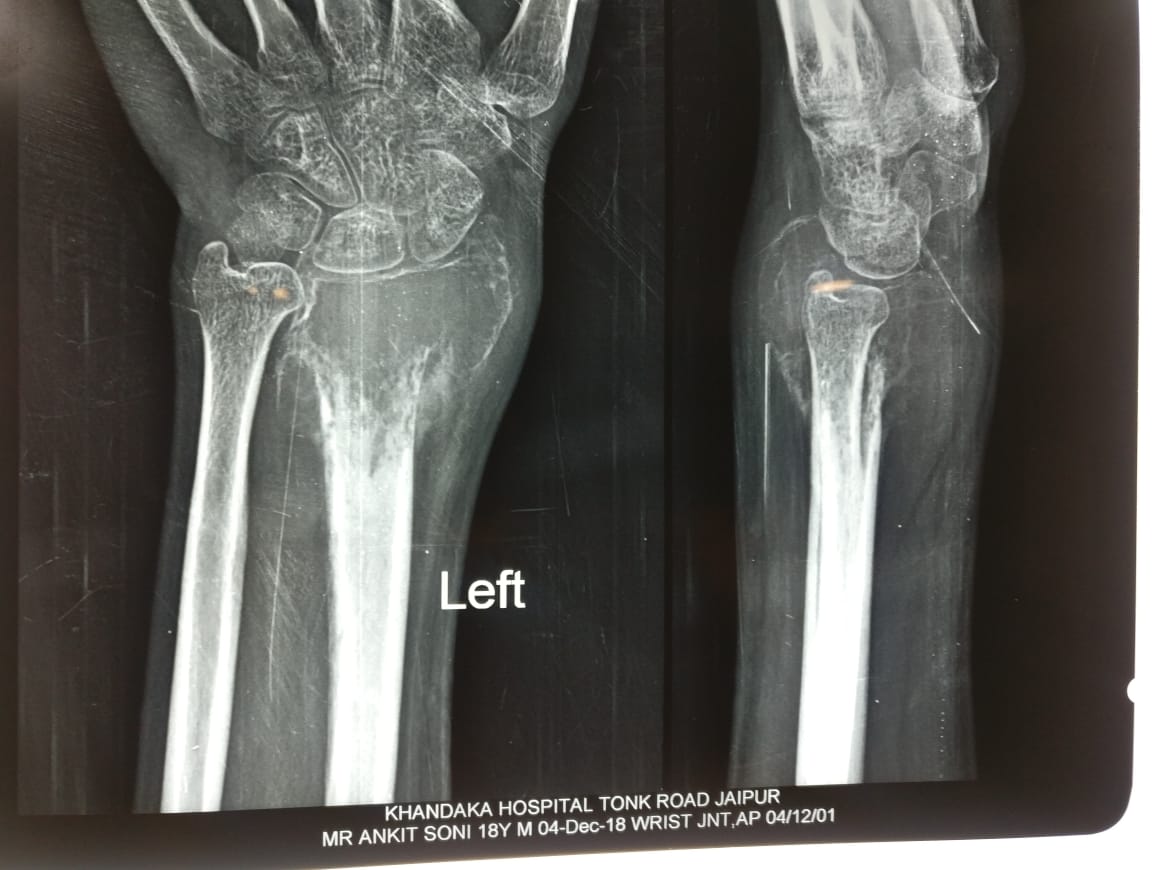

Old transscaphoid perilunar dislocation,proximal Instead of row Carpectomy done

Translocation of Ulna for GCT Of Distal Radius